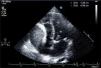

An 82-year-old Caucasian man presented with a history of worsening exertional dyspnea. Two years before the referral he had undergone transapical aortic valve implantation due to severe aortic stenosis. Transthoracic echocardiography was promptly performed: it demonstrated a mild pericardial effusion and a 7.3×4.6 cm homogeneous mass causing extrinsic compression of the right atrium (RA) (Figure 1) and severe functional tricuspid valve stenosis (mean gradient 6 mmHg) (Figure 2). To better define the mass and its relationship with adjacent cardiac structures, contrast chest computed tomography was performed, which confirmed mild pericardial effusion without pericardial thickening and revealed a low-density encapsulated mass arising from the wall of the RA and extending across the right atrioventricular groove (Figure 3), without enhancement.

Figure 1.

Transthoracic echocardiography, apical 4-chamber view, showing a homogeneous mass compressing the right atrium.